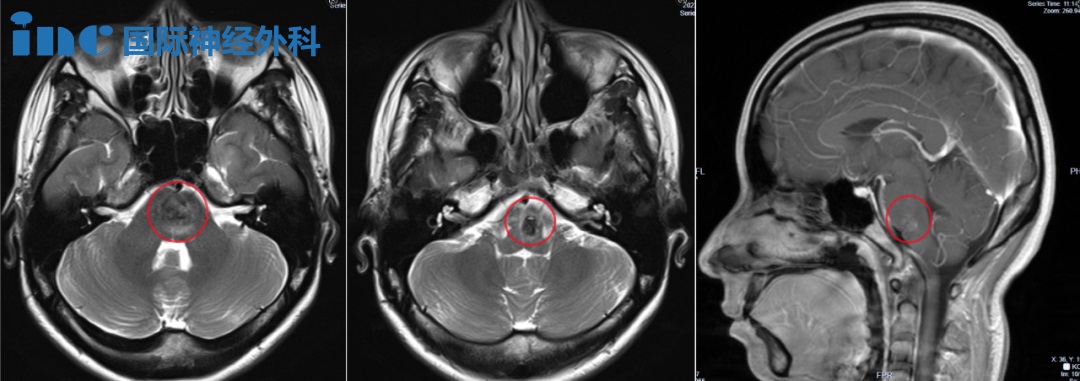

▼2023年9月琳琳核磁影像